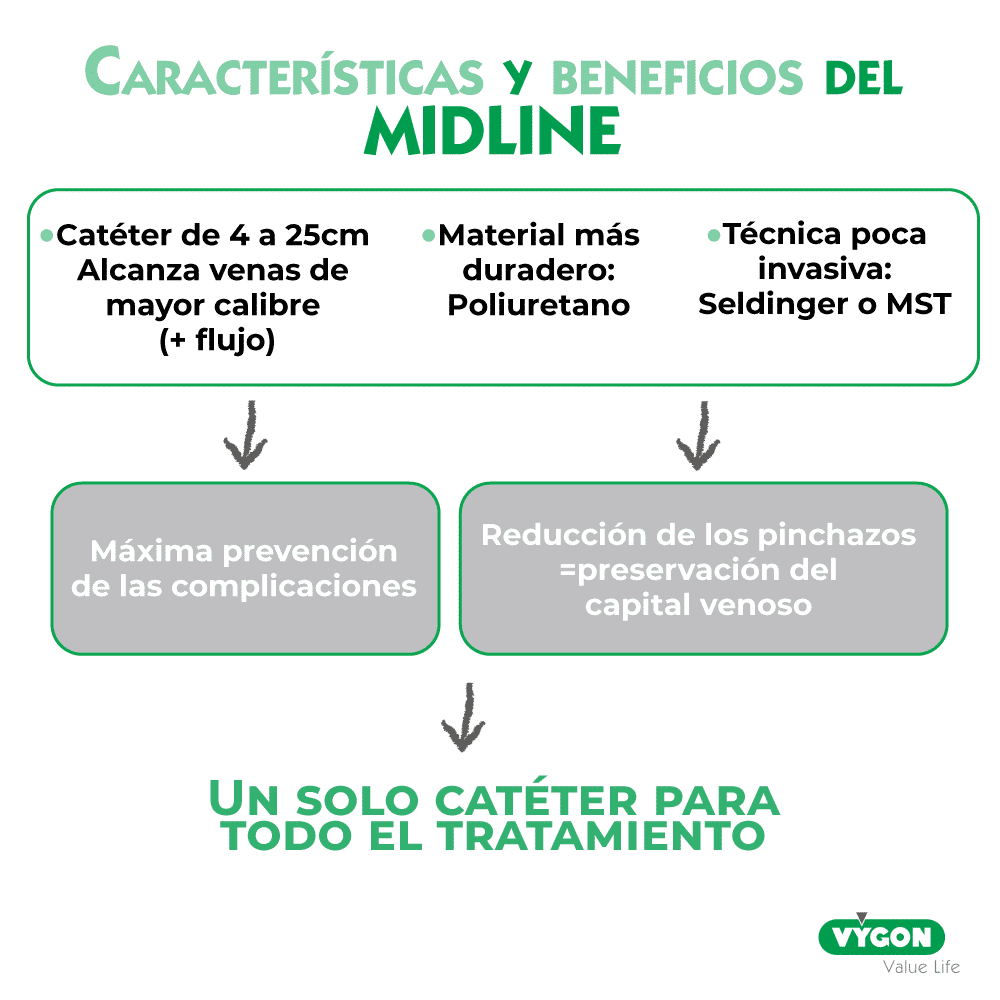

- al ser de material más duradero (poliuretano) permite mantener la misma vía para todo el tratamiento

- su técnica de inserción (Seldinger) es poco invasiva y reduce las complicaciones inmediatas

- la ecografia que acompaña la inserción permite elegir la mejor vena y adecuar el diámetro del catéter a la vena. Lo cual reduce las complicaciones como la flebitis y la trombosis

- al ser un catéter insertado en venas profundas alcanza un flujo importante que permite una administración adecuada de la medicación.

La línea media es un catéter venoso cuya longitud puede variar entre 4 y 30 cm.

Su inserción es periférica y alcanza venas de diámetros importantes, ya que se introduce en el brazo (y no en el antebrazo, como en el caso del catéter corto). La inserción se hace con técnica Seldinger o MicroSeldinger (MST).

Está fabricado en Poliuretano de clase IIa (un mes de duración) o de clase III (duración superior a un mes), material conocido por tener una elevada biocompatibilidad, lo que se traduce en un menor riesgo de lesionar la íntima venosa y una alta resistencia química, por lo que los fármacos no lo debilitan.

Frente a las limitaciones del catéter corto periférico, la línea media permite un acceso vascular periférico que facilita el acceso a un calibre de vena suficiente grande como para evitar las complicaciones relacionadas con una localización muy periférica de la punta del catéter (flebitis, extravasación).

Se trata de un catéter que ofrece una mayor durabilidad y así se pueden reducir los pinchazos.

Ofrece una técnica de inserción lo menos invasiva posible, lo que ayuda a prevenir las complicaciones tempranas: edema, hematoma, malfuncionamiento del catéter, etc.